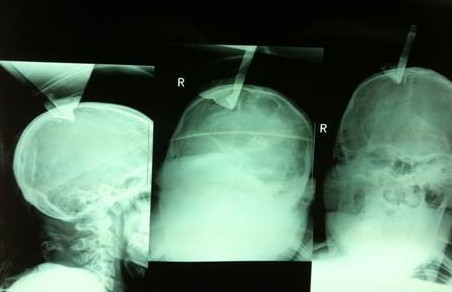

我們先看看這個患者的片子,從片子上很明顯,鋼板穿過了右頂骨造成開放性骨折。